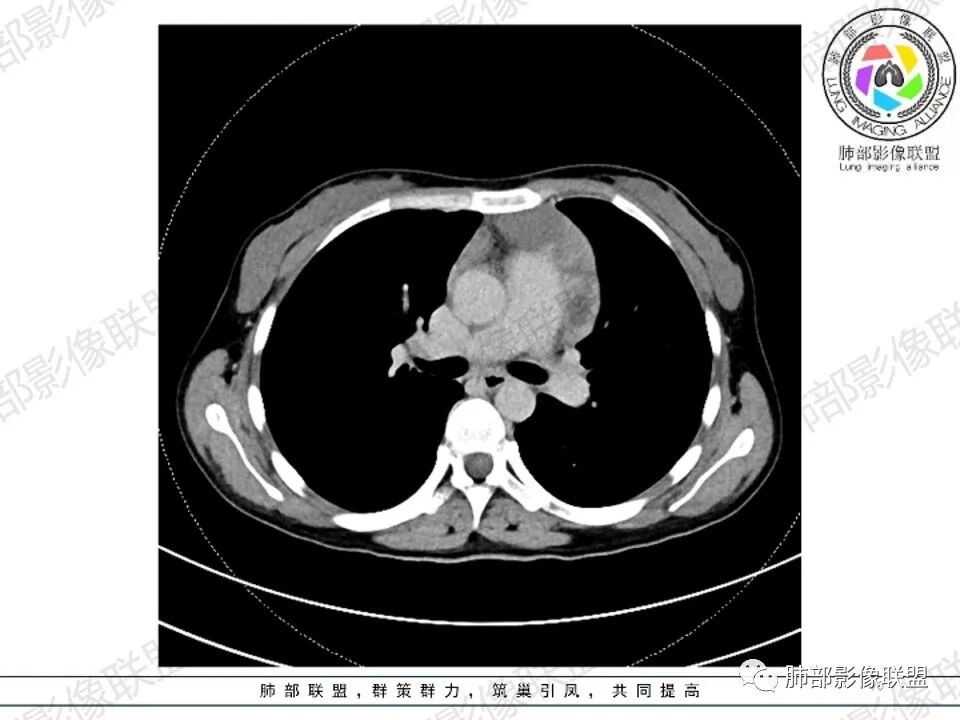

女,27,间断头晕、乏力3年,左眼视物模糊2月。贫血。胸部CT:前纵隔不规则肿块,多结节融合,边界不清,沿主动脉及肺动脉间隙生长,平扫密度欠均匀,增强扫描可见多发低密度坏死,纵隔血管供血穿行,腋窝多发大小不等淋巴结肿大。考虑恶性病变,胸腺癌?肉瘤?淋巴瘤?鉴别胸腺瘤、结节病等。

2.影像显示前纵隔不规则块状影,依势贴附心脏大血管旁,密度不均,边界不甚清楚,有结节融合感。

3.病灶轻度不均匀强化,可见血管穿行,散在液性低密度区。

双肺门未见肿大淋巴结。

4.双侧腋窝区见增大淋巴结,边界清楚。

1.年轻女性,前纵隔不规则块状影,密度不均,边界不甚清楚,有结节融合感,轻度不均匀强化,可见血管穿行,最常见最符合的无疑是淋巴瘤!

3、影像学表现:显著肿大强化的淋巴结,常局限性分布;当患者无或仅轻微症状,纵隔内和腹膜后出现单个慢性巨大肿块,CT平扫示肿块边缘清楚,实质密度均匀,尤其是肿块呈显著强化和邻近大血管一致时,提示本病的可能。即使实质密度不均匀,中心液化坏死,但实质部分呈显著强化,与邻近大血管相似时,在鉴别诊断中仍然要考虑到本病的可能。